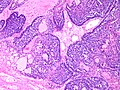

Adenoid cystic carcinoma of the breast

Adenoid cystic carcinoma of the breast. H&E stain. | |

Adenoid cystic carcinoma of the breast is a rare type of breast cancer that is similar to a relatively common tumour of the salivary gland.

Microscopic